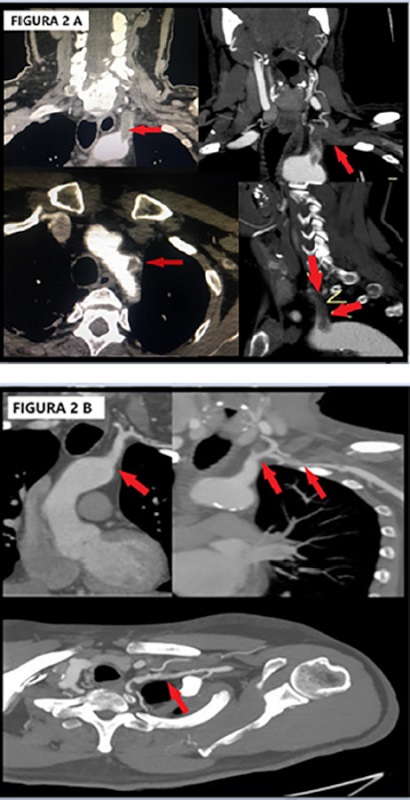

El eco Doppler arterial del miembro superior izquierdo mostró flujo monofásico de muy baja velocidad y resistencia en las arterias humeral, radial y cubital, con trombosis arterial subclavia. Se descartó disección aortica y síndrome de opérculo torácico por angiotomografía de vasos de cuello y cayado aórtico, que mostró trombosis completa arterial subclavia izquierda desde su origen, con parte del trombo intraaórtico, y alteración de la tinción de la arteria vertebral homolateral en segmento intraóseo e intracraneal (Figura 2A).

Por la trombosis completa arterial subclavia izquierda con extensión intraaórtica asociada a accidente cerebrovascular posterior isquémico, se descartó el tratamiento endovascular o quirúrgico por el alto riesgo de complicaciones embolicas sistémicas y se decidió anticoagulación con heparina sódica por bomba de infusión continua, bajo estricto control neurológico y posterior rotación a acenocumarol vía oral. Al día 10 se fue de alta sin complicaciones neurológicas, ni isquémicas en el miembro superior. Al año se suspendió la anticoagulación debido a hematuria y hematemesis reiteradas, y continuó con clopidogrel y cilostazol vía oral. El último control a los 3 años por angiotomografía evidenció recanalización parcial de la trombosis subclavia, con desaparición total del trombo intraaórtico en el ostium subclavio. (Figura 2B)